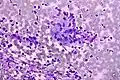

Adenocarcinoma colorretal. Coloração de Field. -

Granuloma. Coloração de Field.